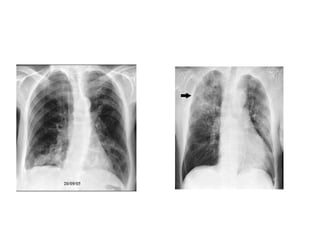

DIAGNOSIS

• Clinical history, risk factors & CXR

• CXR is must

• CT Scan may be required